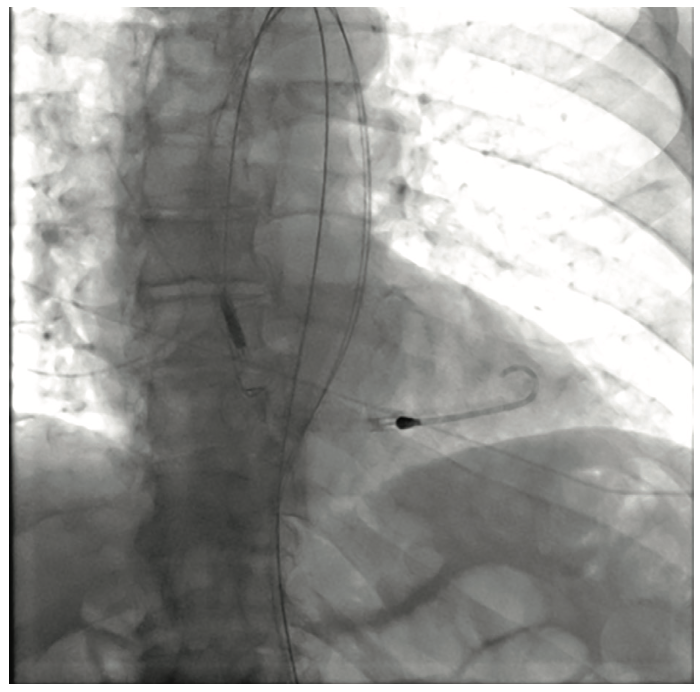

The initial interventional attempt via a transradial approach was unsuccessful due to significant vessel tortuosity. Therefore, a high risk protected PCI was attempted via left femoral access using an Impella 2.5L device (Abiomed) for left ventricular support. The Impella 2.5L was placed via the right femoral access. Before the engagement of coronary arteries, the patient had deteriorated clinically with hypotension and Impella support dropping to 1.4L. Subsequently, the patient went into VT/VF arrest, requiring cardiopulmonary resuscitation (CPR). The patient was emergently intubated. During active CPR and VT storm, selective injections of the left main coronary artery were performed, revealing total thrombotic occlusion of distal left main artery. The patient underwent multiple percutaneous transluminal coronary angioplasties of the left main, ostial and mid LAD, and LCx (OM1) lesions. This was then followed up with stenting of the mid left main into the ostial LAD and LCx (OM1) branch. The coronary interventions were performed during CPR. The patient received a total of 13 defibrillator shocks, and was given intravenous amiodarone and lidocaine pushes during CPR. Return of spontaneous circulation was obtained after 45 minutes. Due to extensive PAD, the Impella device was removed and an intra-aortic balloon pump was placed via a left femoral approach for continued hemodynamic support.